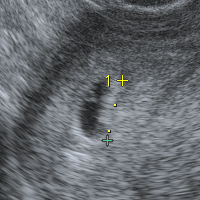

Bt18 5週2日 胎嚢確認 Higashinoの日記 2度の流産をのりこえて

5週0日 胎嚢確認 37歳 長い不妊治療と戦い出産 流産2回経験

転院 K Clinic五周期目 Bt17 5週と0日 胎嚢確認 隣の見えないコウノトリ 33歳下垂体性無月経の1人目日記